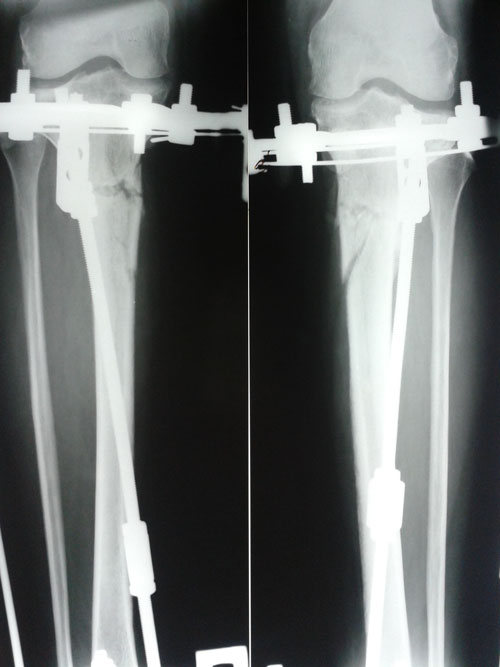

Рентген в 60 дней с момента операции.

Сращение идёт хорошо, костная мозоль растёт.